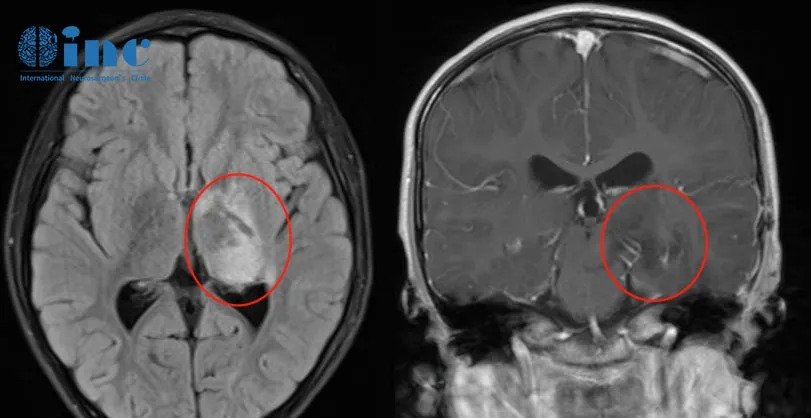

第一次术后MRI

术后2年,左侧颞叶处发现10.7cm结节,且还在增大

可可和残余的肿瘤和平共处了2年,然而复查MRI发现左侧颞叶附近有一小结节病灶增大,术前6mm,现11.1mm,已明确复发,是手术未注意的残留,但在增大。